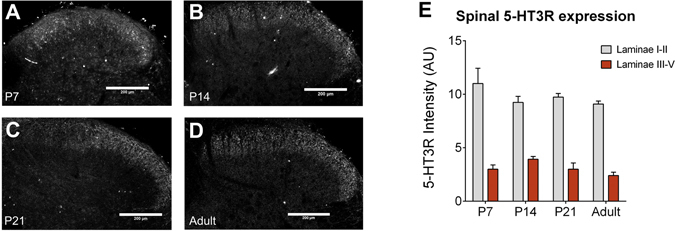

We next tested whether 5-HT3Rs, which are primarily expressed on excitatory dorsal horn interneurons in addition to primary afferent neuron terminals29, 30, play a role in serotonergic facilitation of dorsal horn tactile processing. Immunohistochemical experiments demonstrated that 5-HT3Rs are expressed in the superficial spinal dorsal horn from P7, and their distribution does not change with age (Fig. 3).

Figure 3.

5-HT3 receptors are expressed in the lumbar dorsal horn from P7. Immunohistochemical labelling of 5-HT3R was performed at P7 (A), P14 (B), P21 (C) and in adults (D). Scale bar = 250 μm. 5-HT3R labelling was observed predominantly in laminae I-II in the dorsal horn from P7 and this distribution did not change with age. Quantification of 5-HT3R intensity was performed in laminae I-II and in laminae III-V and revealed no change in 5-HT3R intensity with age (E). Bars indicate mean ± SEM.